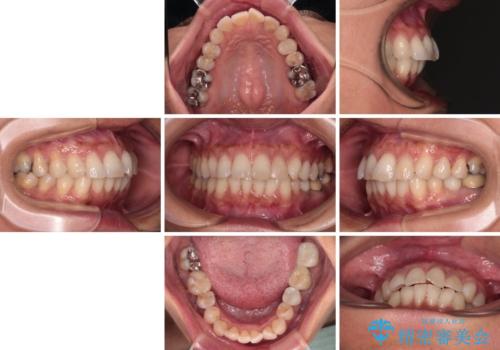

むし歯と前歯のデコボコを治したい インビザラインを使用した総合歯科治療

- 目立つ銀歯やむし歯、前歯のデコボコを気にして来院された患者様です。

デコボコはある程度改善できれば良いとのことでしたので、インビザラインの廉価版を用いて矯正治療を行うこととしました。

飛行機での通院であり、更にはご家族がの都合で海外に滞在されることも多いため、中等度の歯列不正に対応可能なインビザライン・モデレートパッケージを使用することとしました。

むし歯治療は、症状のある歯を矯正治療前に処置し、概ね歯列が整ったところで残りのは全て処置し、最後にインビザラインで歯列を仕上げることで、無駄なく治療を進めて行くこととしました。

しっかりと装着時間を守ってくださり、来院のタイミングに合わせてインビザラインの装着期間を調整するなど、協力いただいたおかけで、1年半の期間で全てを終えることができました。